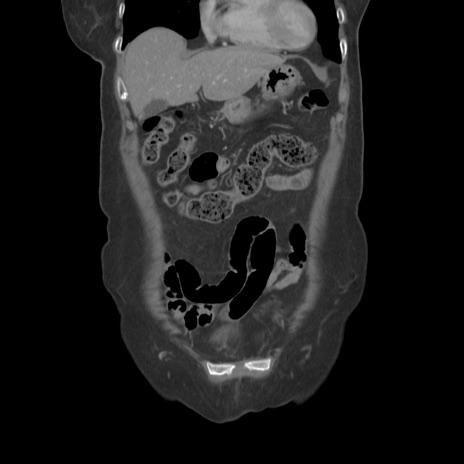

症例19(冠状断像)

【症例】80歳代女性

【主訴】下腹部痛

【現病歴】約8時間前より下腹部痛の出現あり、救急外来受診。

【既往歴】両側付属器切除

【身体所見】意識清明、下腹部正中に手術痕あり、その部位に一致して圧痛と反跳痛あり。腸蠕動音は亢進。

【データ】WBC 9300、CRP 0.15